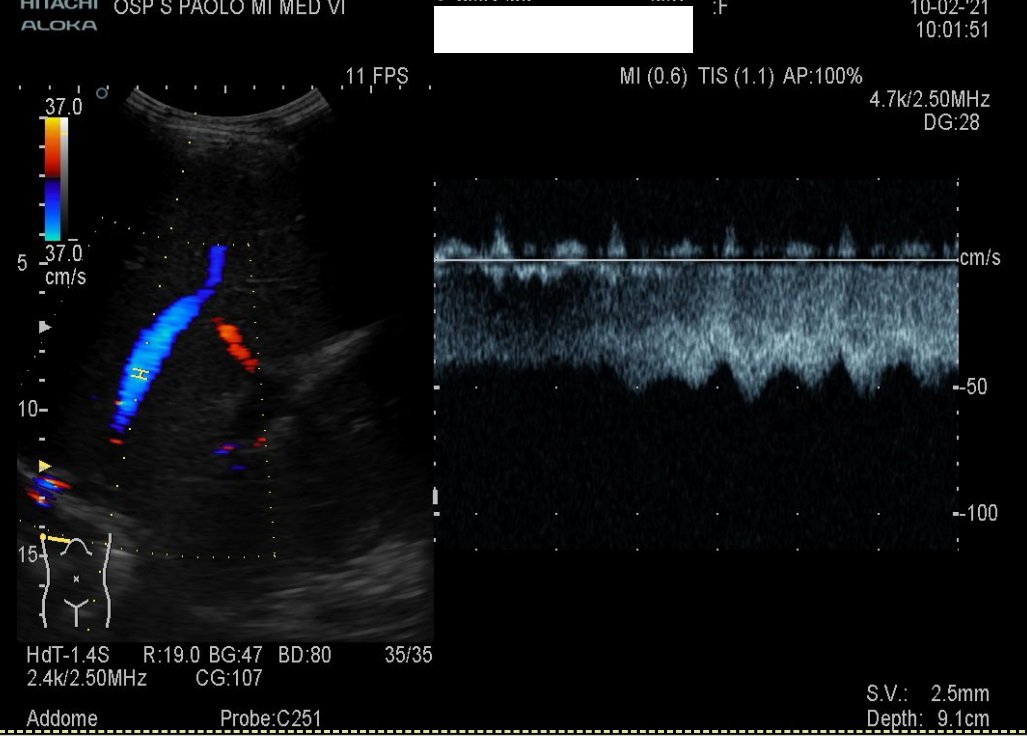

Doppler techniques can be used to

reveal an unspecific hyperdynamic state in hepatic vessels with a higher diastolic arterial

blood flow when compared with healthy individuals.

Owing to oedema and narrowing of the hepatic veins, the flow pattern is often

non-triphasic